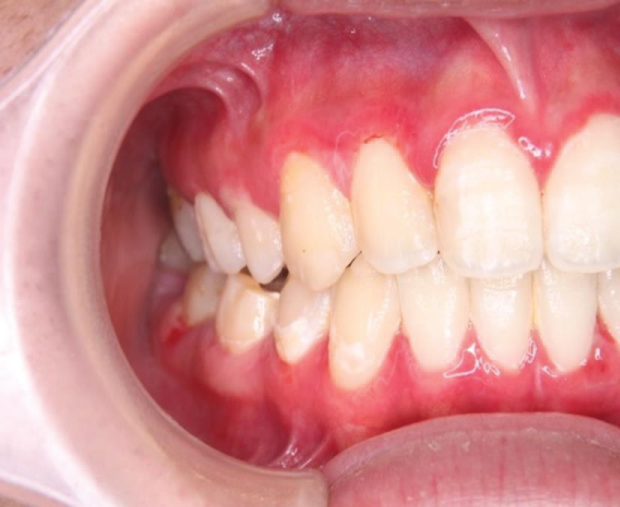

An 18-year-old female patient visited our clinic with a complaint of gingival bleeding that had persisted for more than 2 months. She had no reported medical and dental problems. There was no remarkable family medical history. Before visiting our hospital, the patient had been treated with topical corticosteroid and oral antibiotics, but improvement was not observed. Physical examination revealed fiery red, glazed, atrophic, or eroded-looking gingivae and ulcer formation at the interdental papillae. Bleeding from the gingivae was easily induced by contact with a cotton swab, and the epithelium was easily peeled off, resulting in bleeding from the ulcer surface (Figure 1). Due to the pain caused by tooth brushing, she could not maintain adequate oral hygiene, and the deposition of dental plaque and calculus formation were observed on the labio-buccal side of the upper and lower teeth. Because of bleeding by probing, full mouth periodontal condition was not evaluated. No particular bulla lesions and no white linear or reticular lesions in other areas of the oral mucosa were observed. The diagnosis was inflammatory and immune-mediated gingival disease. There were no ocular, pharyngeal, or skin lesions.

Figure 1: Gingivitis affecting both the upper and lower gingivae. Ulcers were observed at the interdental papillae in the right lower premolar region. Plaque accumulation on the labio/buccal surface of the teeth. View Figure 1